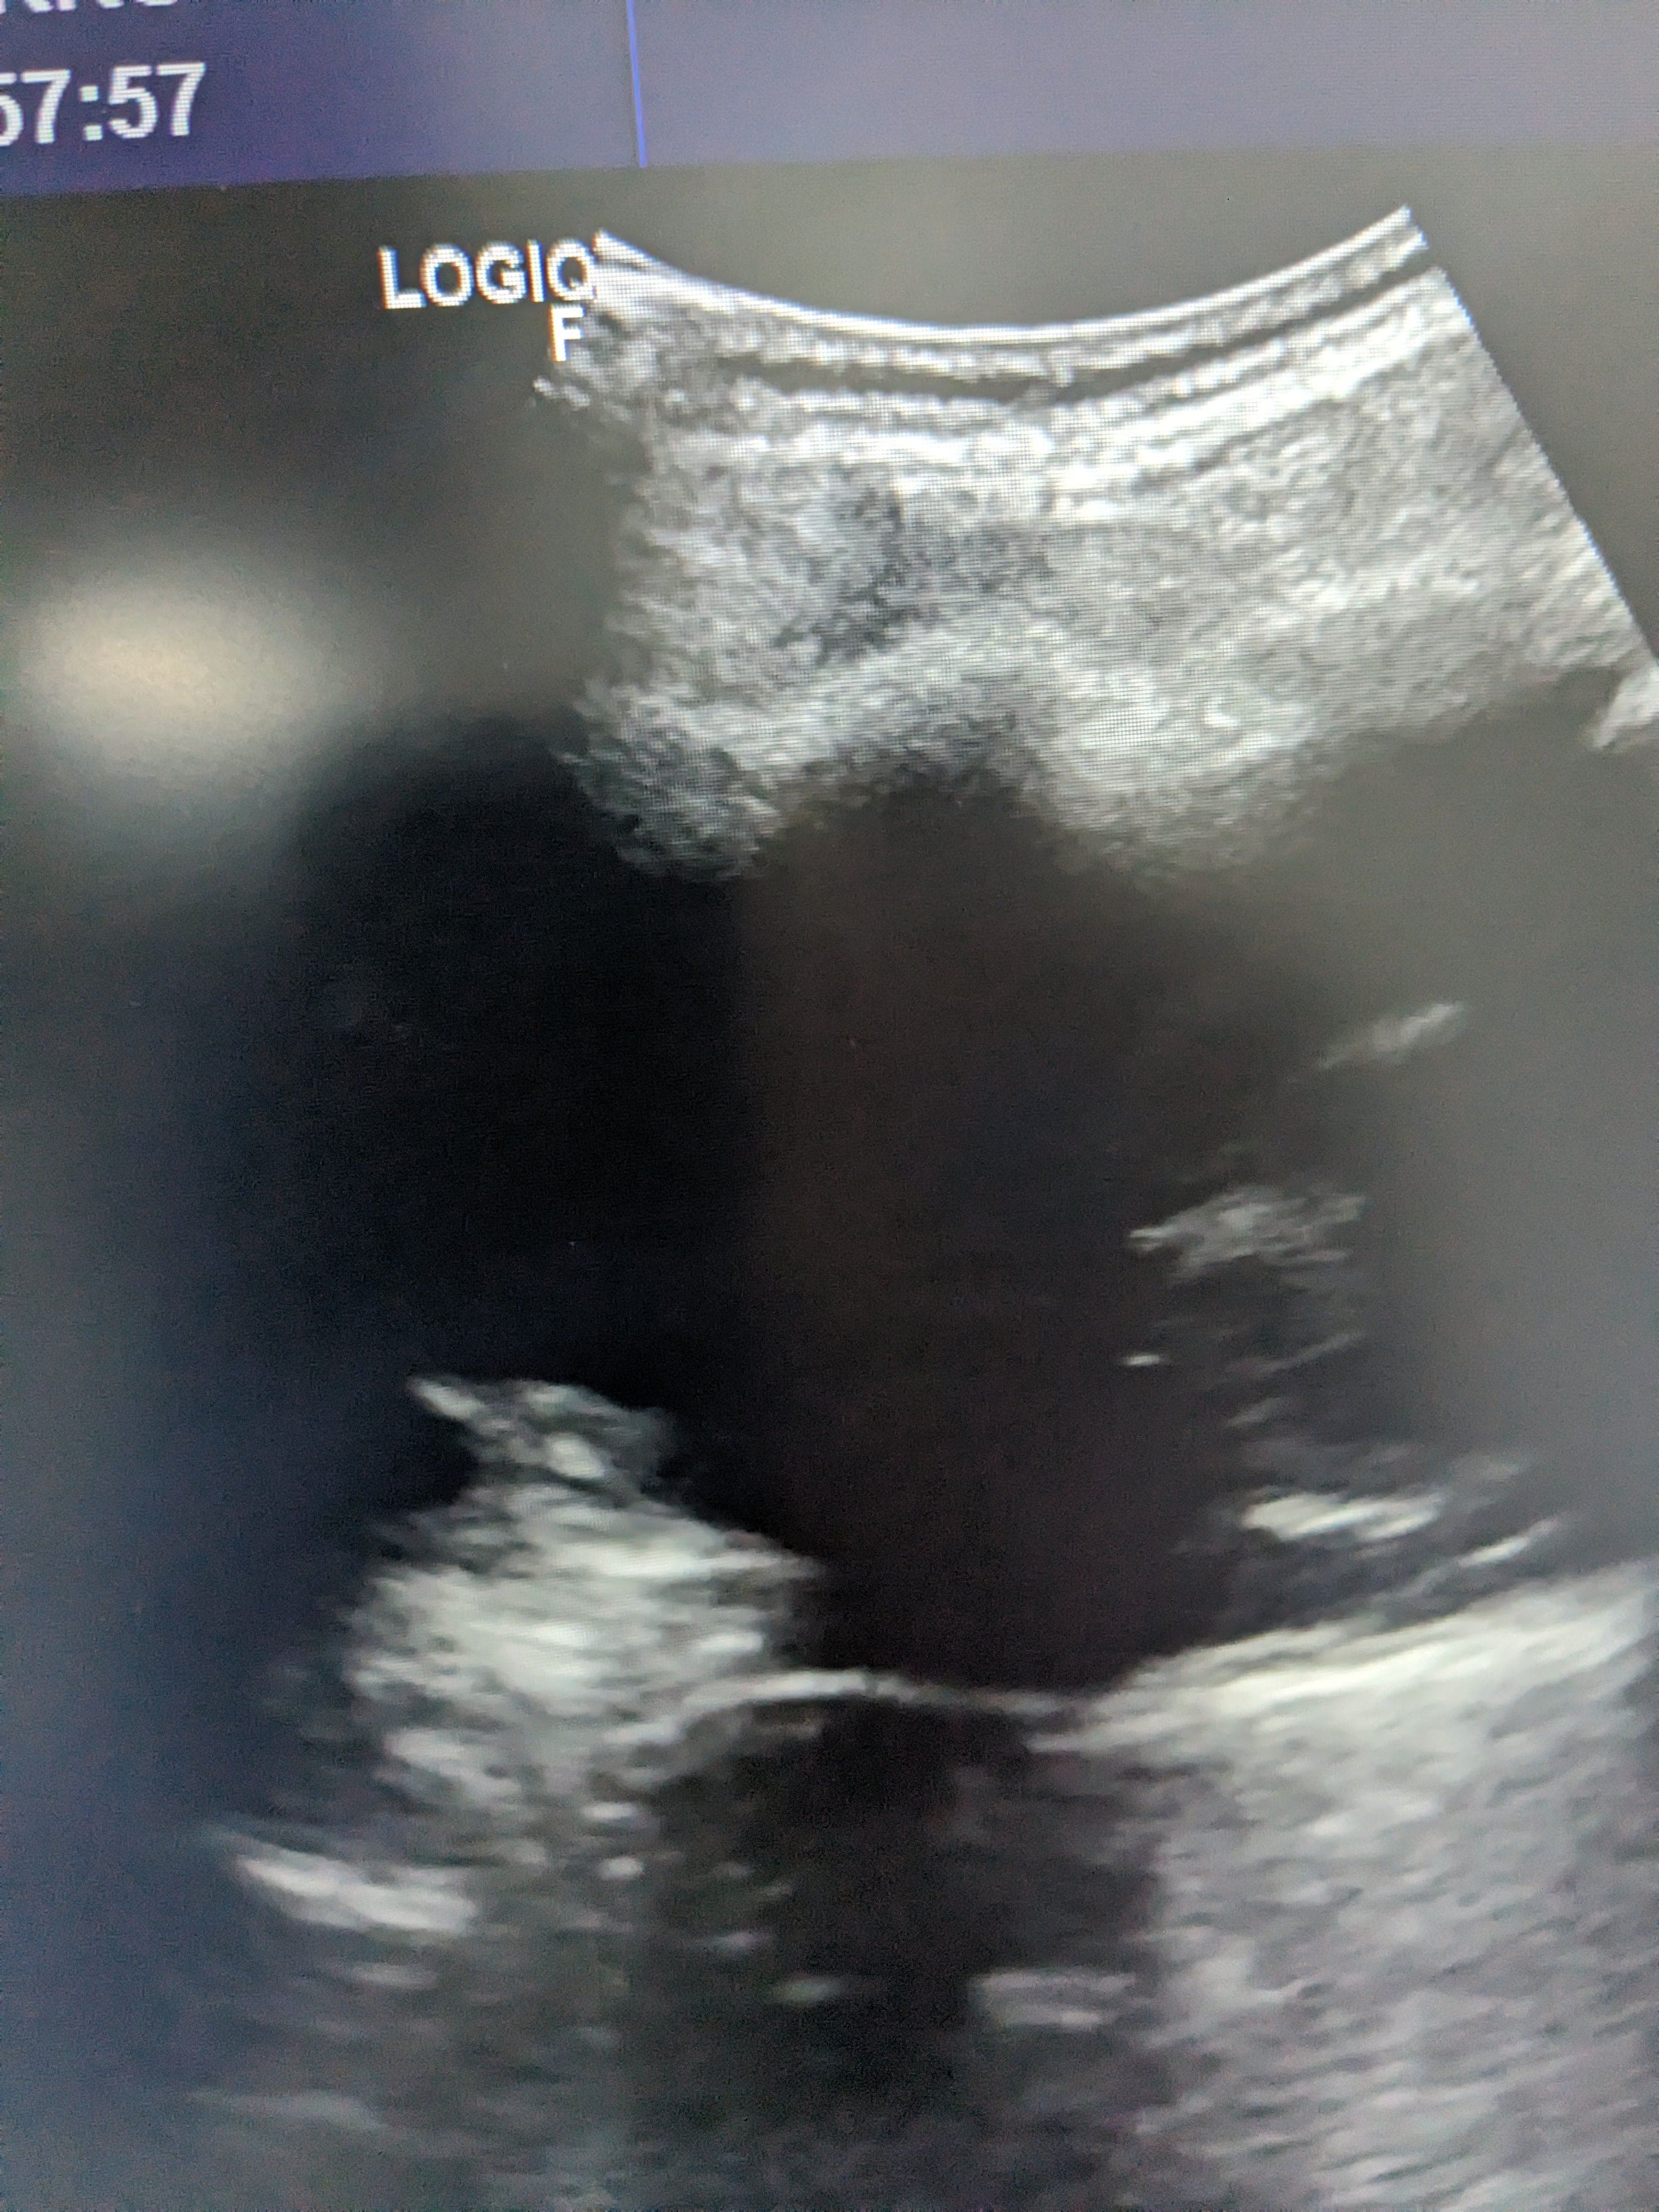

Se hace ecografía clinica en la consulta de atención primaria, observamos derrame pleural en pulmón izquierdo hasta medio campo pulmonar.